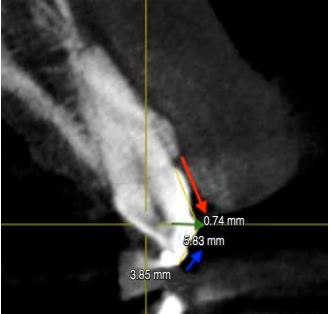

En el examen radiográfico tridimensional se procede a dividir la corona del diente en dos partes trazando dos líneas: Línea A (se mide en mm del tope de resina fluida al borde incisal [BI] del diente) y una Línea B (se mide en mm desde el UCE al tope de resina fluida), se suma la línea A más la línea B para dar como resultado la longitud de la corona dental (Figura 6) (Tabla 2).

Figura 6 Vista transversal en cone-beam computed tomography de pieza 2.1, en la que flecha roja: línea B (5.83 mm); flecha azul: línea A (3.85 mm); y flecha verde: medida del tope de resina (0.74 mm).

| 2.1 | 3.85 | 5.83 | 9.68 |

A los resultados del CBCT de la longitud de la corona dental se le resta la medida del tope de resina, con el objetivo de tener como resultado el tamaño real de la corona anatómica. El tamaño del tope de resina de cada diente se logró midiéndolo en la tomografía 3D como se puede observar en la Tabla 3.

| 2.1 | 9.68 | 0.74 | 8.94 |